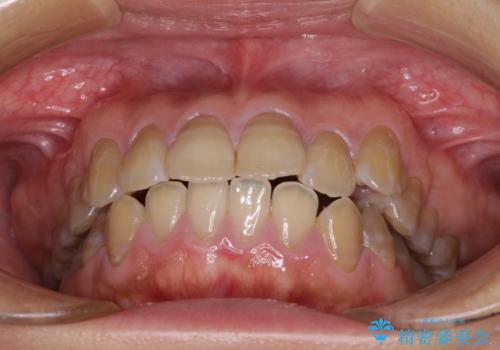

- 口元の突出感を気にして来院された患者様です。

上下前歯が著しく前突している状態であったので、上下左右の第1小臼歯4本を抜歯し、ワイヤー装置にて矯正治療を行うこととしました。

舌の突出癖により、前突になったと考えられたため、舌のトレーニングをしっかりと行うよう指導しました。